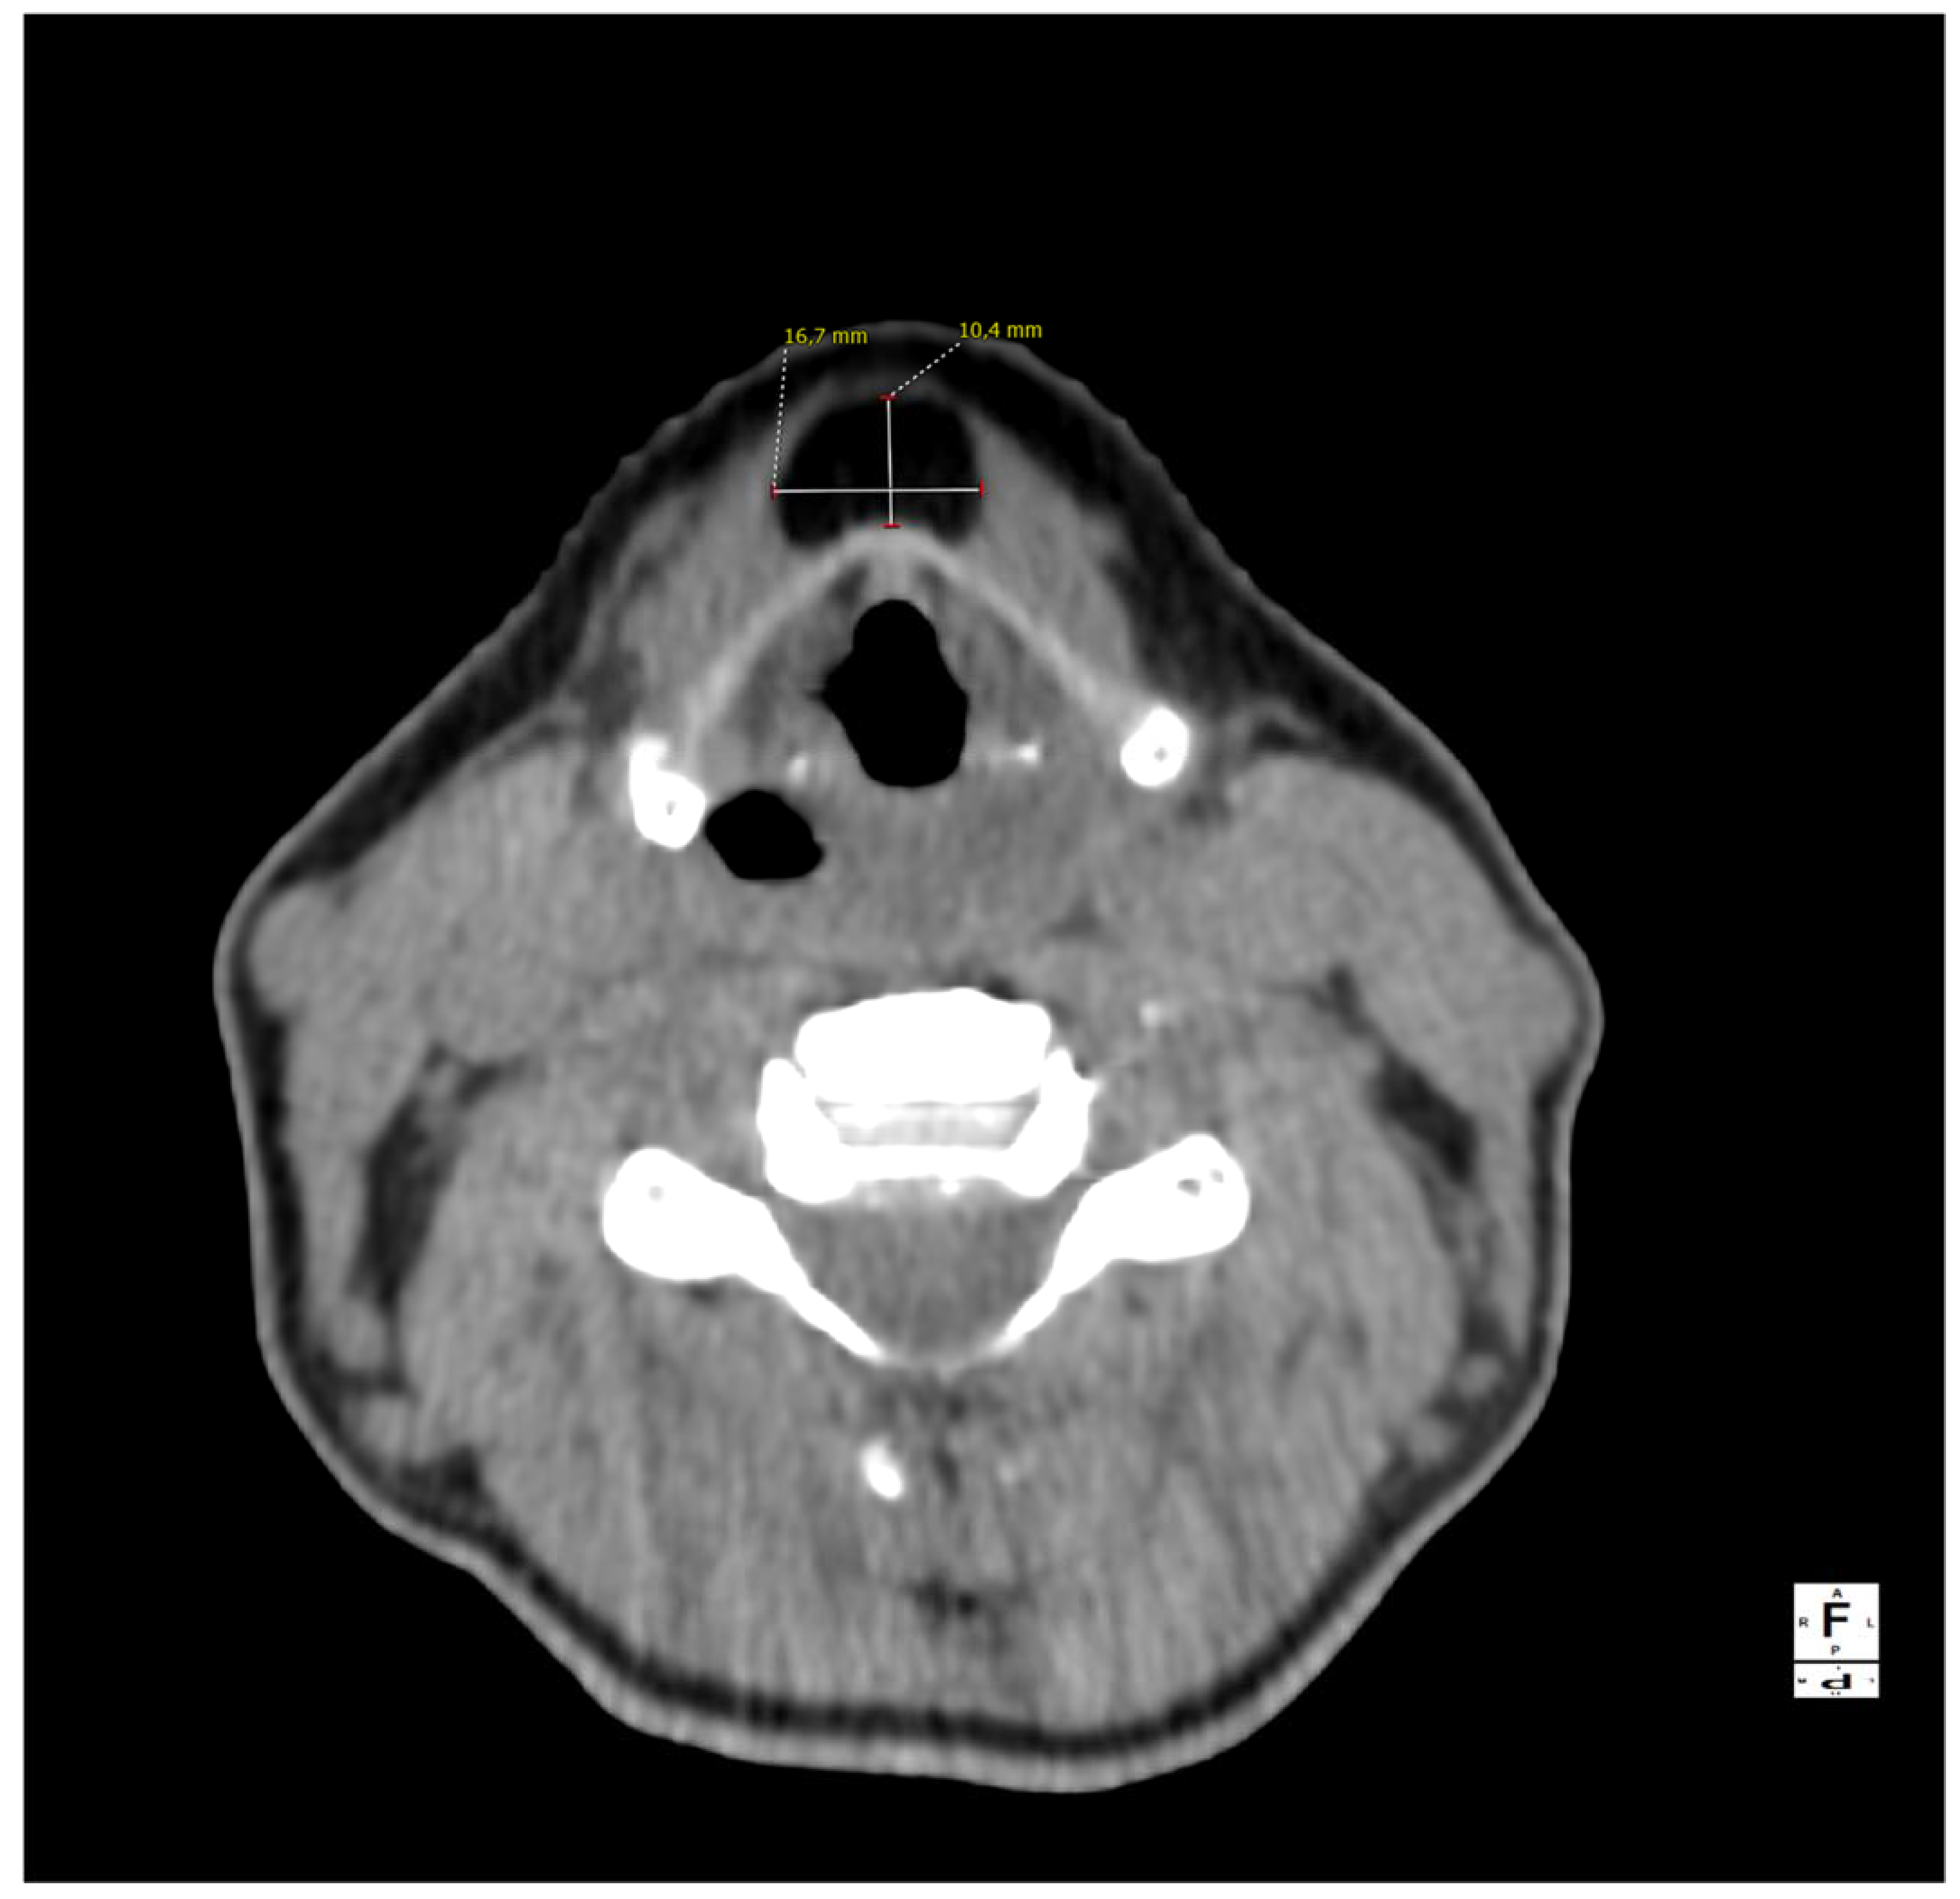

Figure 1.

A computed tomography of the neck on the axial plane demonstrating a 10 × 17 × 38 mm (AP × LL × CC) lesion and its relationships with the anterior border of the thyroid cartilage of the larynx. The anatomical subsite pinpoints to a possible persistence of the thyroglossal duct (TGD). This represents an embryological remnant during the migration of the endodermal thyroid diverticulum, and it may extend from the foramen cecum of the base of the tongue to the suprasternal notch [1,2,3]. TGD can variably persist in up to 7% of the adult human population, and its incomplete obliteration (usually by the tenth week of gestation) leads to the creation of the pyramidal lobe of the thyroid gland as well as many other neck disorders, including lingual thyroiditis and TGD cyst [4]. The latter in particular is the most frequent congenital central neck mass and it usually presents around 30–40 years of age as an infected cyst (more rarely as a fistula or a sinus), causing neck discomfort and dysphagia [5,6]. Their treatment usually consists of open surgical excision along with the central portion of the hyoid bone’s body and a core of tongue musculature, as described in 1920 by Walter E. Sistrunk from the Mayo Clinic [7]. The differential diagnosis of TGD cysts and midline masses is vast and it includes, among others, dermoid and epidermoid cysts, cystic nodal metastases of papillary thyroid carcinoma, lymphangiomas, lymphomas, ectopic thyroid adenomas, or lipomas [4,8].